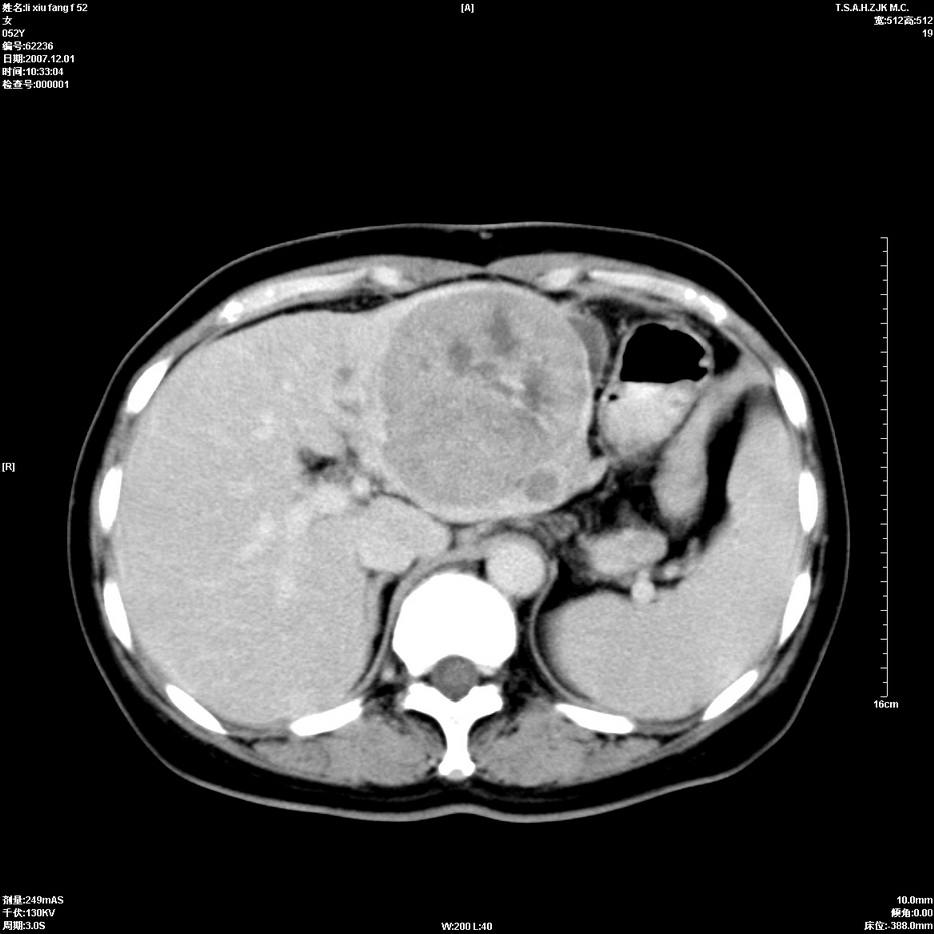

标题: CT12858:女,52岁,胎甲球蛋白861肝左叶占位,肝癌。下腔静 [打印本页]

标题: CT12858:女,52岁,胎甲球蛋白861肝左叶占位,肝癌。下腔静

肝左叶巨大低密度灶肿块,增强符合快进快出表现,有动静脉交通支;静脉期,下腔静脉内有充盈缺损,afp明显升高,支持肝癌并下腔静脉癌栓形成。

以下是引用拾荒者在2008-4-15 22:57:00的发言:[br]肝左叶巨大低密度灶肿块,增强符合快进快出表现,有动静脉交通支;静脉期,下腔静脉内有充盈缺损,afp明显升高,支持肝癌并下腔静脉癌栓形成。